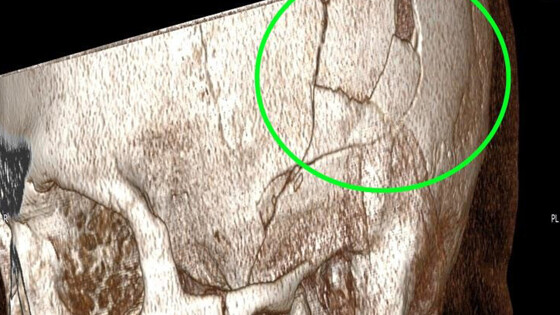

Пациента доставили в больницу с рабочего места, где он занимался ремонтом «КамАЗа», когда ему на голову упала коробка передач весом 200 кг. Он получил тяжелую травму с повреждением костей и смещением костных фрагментов в полость черепа.

Требовалось срочное хирургическое вмешательство, врачам пришлось заново собирать черепную коробку. Нейрохирургам удалось восстановить целостность черепа без применения имплантов и внешних вставок.